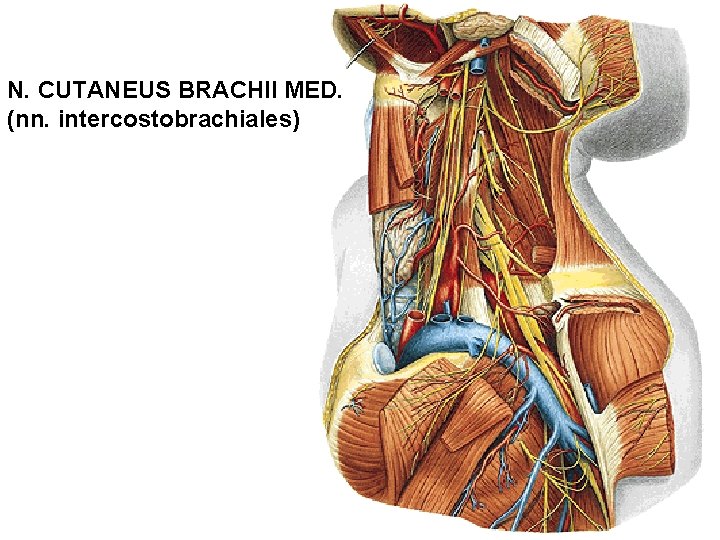

N. CUTANEUS BRACHII MED. (nn. intercostobrachiales)